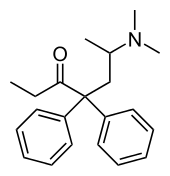

Amidones

- Dextromethadone

- Dipipanone

- Isomethadone=

- Levoisomethadone

- Levomethadone

- Methadone

- Methadone intermediate

- Normethadone

- Norpipanone

- Phenadoxone (heptazone)

Structures

| Amidones | ||||

|---|---|---|---|---|

|

|

|

Levoisomethadone Levoisomethadone | |

Noracetylmethadol Noracetylmethadol |

Levomethadone Levomethadone |

Methadone Methadone |

Methadone intermediate Methadone intermediate | |

Normethadone Normethadone |

Norpipanone Norpipanone |

Phenadoxone Phenadoxone |

Pipidone Pipidone | |